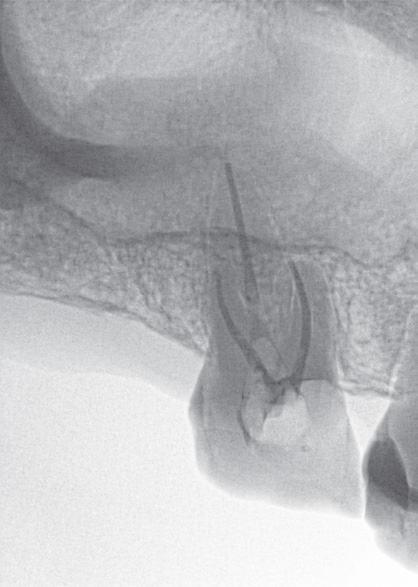

If I'm doing a root canal, the inversion function is especially helpful (see pictures, at right). Sometimes, the apex of the tooth is not easy to define on a multirooted tooth, so in those cases I use the “invert” tool with a trial gutta-percha, which makes it easier to see.

Dr. Mahallati inverts his Schick 33 images to offer greater definition.